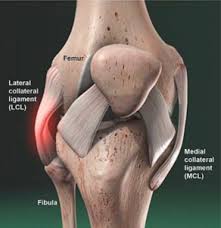

Grade 2 Ligament Tear Knee : Acl Vs Mcl Tears What Are The Differences Heiden Orthopedics - This means there have been larger tears in the ligament, but it is not completely torn.. Grade 3 these are severe, often involving a complete tear of the ligament. Nevertheless, ligament injuries account for up to 40 percent of all knee injuries, and of these, medial collateral ligament (mcl) injuries appear to be the most common. It occurs when the injury affects more than just the medial collateral ligament (mcl) and may require surgery. A grade 3 mcl tear often occurs along with a tear of the anterior cruciate ligament. With a grade 2 lcl sprain, you will have significant tenderness on the outside of your knee, over the lateral ligament.

You will likely have some swelling. Some surgeons describe a grade four injury, also called a medial column injury, to the mcl. Grade one indicates a mild injury, grade two indicates a partial tear, and grade three indicates a complete tear. Ideally, people who sustain grade 1 and grade 2 lcl injuries can begin early movement of the knee joint. Grade 2 acl injuries are rare and describe an acl that is stretched and partially torn.

This injury represents an incomplete (grade ii) or a complete (grade iii) rupture of the collagen fibers which connect the ends of the femur (thigh bone) and the tibia (shin bone). Ideally, people who sustain grade 1 and grade 2 lcl injuries can begin early movement of the knee joint. 36 years experience orthopedic surgery. A grade 2 sprain stretches the ligament to the point where it becomes loose. Grade one indicates a mild injury, grade two indicates a partial tear, and grade three indicates a complete tear. Ligament is completely torn, often along with a sprain of the acl or other knee ligaments. How long willit take for an mcl grade 2 knee ligament tear to heal completely without further damage? Grade 3 these are severe, often involving a complete tear of the ligament.

In grade one injuries, the pcl retains the ability to stabilize the knee joint. Image of a man with an mcl tear. You may feel instability of the knee and pain with movement. This means there have been small tears in the ligament. When the knee is bent to 30 degrees and an outward force applied to the lower leg to stress the medial ligament, pain is felt but there is no joint laxity (play valgus stress test video). Graded 1, 2 or 3 depend on on severity of the injury. You will likely have some swelling. There is damage to a more extensive number of collagen fibres. Grade 3 lcl sprain (severe) grade 3 is the condition where ligament is completely torn, which causes swelling and sometimes bleeding underneath the skin. Grade 1 and grade 2 lcl tears involve damage to the ligament however there is not a complete disruption of the fibers of the entire ligament. Rehabilitation after injury to the medial collateral ligament of the knee phase 1: This usually causes some instability in your knee joint. Your symptoms will depend on the level of your injury.

Some surgeons describe a grade four injury, also called a medial column injury, to the mcl. There is major pain, tenderness and swelling on the inner side of the knee. Grade i is sprained, grade ii is a partial tear, grade iii is a complete tear of the ligament. Grade 2 — noticeable looseness in the knee (the knee opens up about 5 millimeters) when moved by hand. With a grade 2 lcl sprain, you will have significant tenderness on the outside of your knee, over the lateral ligament.

As a result, the joint may show abnormal looseness. A grade 2 sprain stretches the ligament to the point where it becomes loose. Some surgeons describe a grade four injury, also called a medial column injury, to the mcl. (minor sprain) high signal is seen medial (superficial) to the ligament, which looks normal grade 2: Partial tear of the ligament, leaving a small feeling of instability. This usually causes some instability in your knee joint. Some mild knee tears may not limit your ability to walk or cause serious discomfort. Grade 2 symptoms are considered moderate with significant pain and tenderness on the inside of the knee with some swelling.